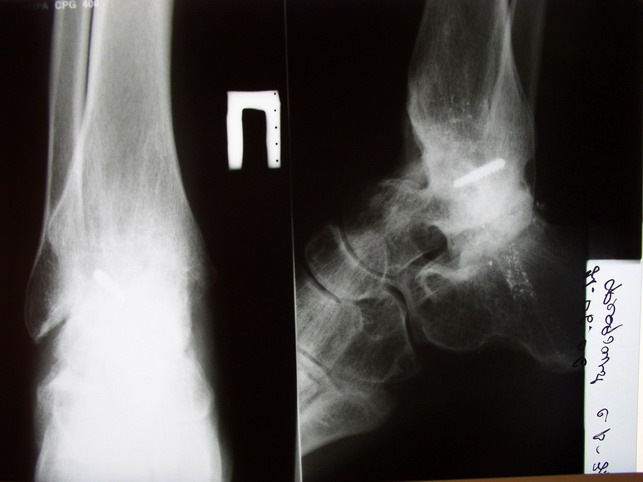

Ваша дискуссия заставила перелистать свои наблюдения.

Среди повреждений таранной кости (Hawkins III-IV) с одновременной травмой лодыжек встретилось следующее (см. вложение). Пациент упал в колодец на глубину 10 метров (Х.2002 г.), госпитализирован с диагнозом: з/перелом шейки правой таранной кости (Hawkins IV) с переломовывихом тела назад и кнутри, закрытый перелом внутренней лодыжки и переднего края большеберцовой кости. Оперирован в первые 12 часов после травмы, выполнена открытая репозиция таранной кости, внутренним и передне-внутренними доступами, остеосинтез переломов шейки и тела губчатыми винтами, для реваскуляризации тела таранной кости первичный компрессионный над- и подтаранный артродез. Синтез внутренней лодыжки губчатым винтом. Удаление винтов через 1 год,2 мес. Получен анкилоз указанных суставов с сохранением длины конечности, полная реваскуляризация таранной кости, о чем говорит сращение ее переломов, отсутствие отеков и

цианоза стопы и голени. Компенсаторная подвижность переднего и среднего отделов стопы около 15-20 градусов за счет поперечного (Шопара) сустава стопы. Считаю оправданной подобную тактику, не смотря на угрожаемый прогноз (100% асептический некроз) по классифицкации Hawkins.